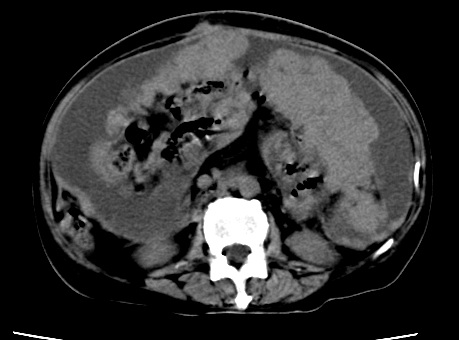

标题: CT23975:女61岁,腹部不适,明显消瘦

既往5年前卵巢癌行子宫及附件切除,右乳癌术后一年,考虑腹膜转移?

大量腹水,考虑腹膜转移。肝脏低密度灶。1囊肿,2转移。

1)结合病史,考虑腹膜及网膜转移瘤。2)肝脏多发性低密度灶,不排除转移瘤。3)大量腹水。

考虑卵巢癌行子宫术后复发,并肝、腹腔 、大网膜转移可能性大。

大量腹水。